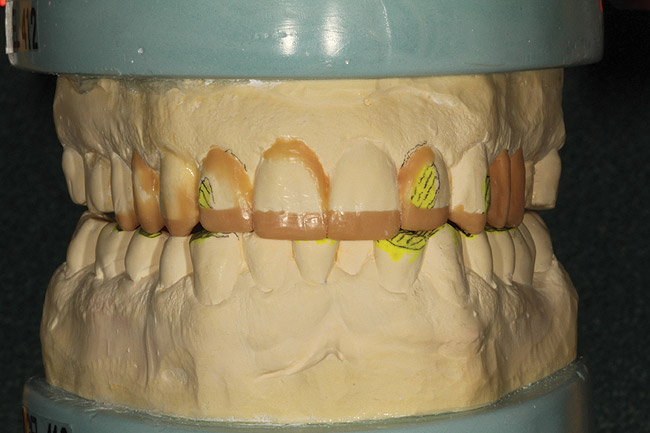

A centric bite registration was taken after the patient had worn an anterior deprogrammer for several days (Figure 3). Proper vertical dimensions were further established using upper and lower incisor cemento-enamel junction (CEJ) to CEJ measurements from digital calipers.9 This information enabled the ceramist to mount the case in centric relation and correct the patient’s vertical dimension. With the addition of clinical photographs, the ceramist produced a precision wax-up (Figure 4).

Figure 13  The additive-reductive model was completed by adding wax to the negative areas.

Figure 13

Figure 14  The mandibular preoperative model was reduced so that the restorations being fabricated on the maxillary arch could conform to the proper curves.

Figure 14

Figure 15  A reduction stent was created to transfer this information to the patient’s mandibular arch.

Figure 15